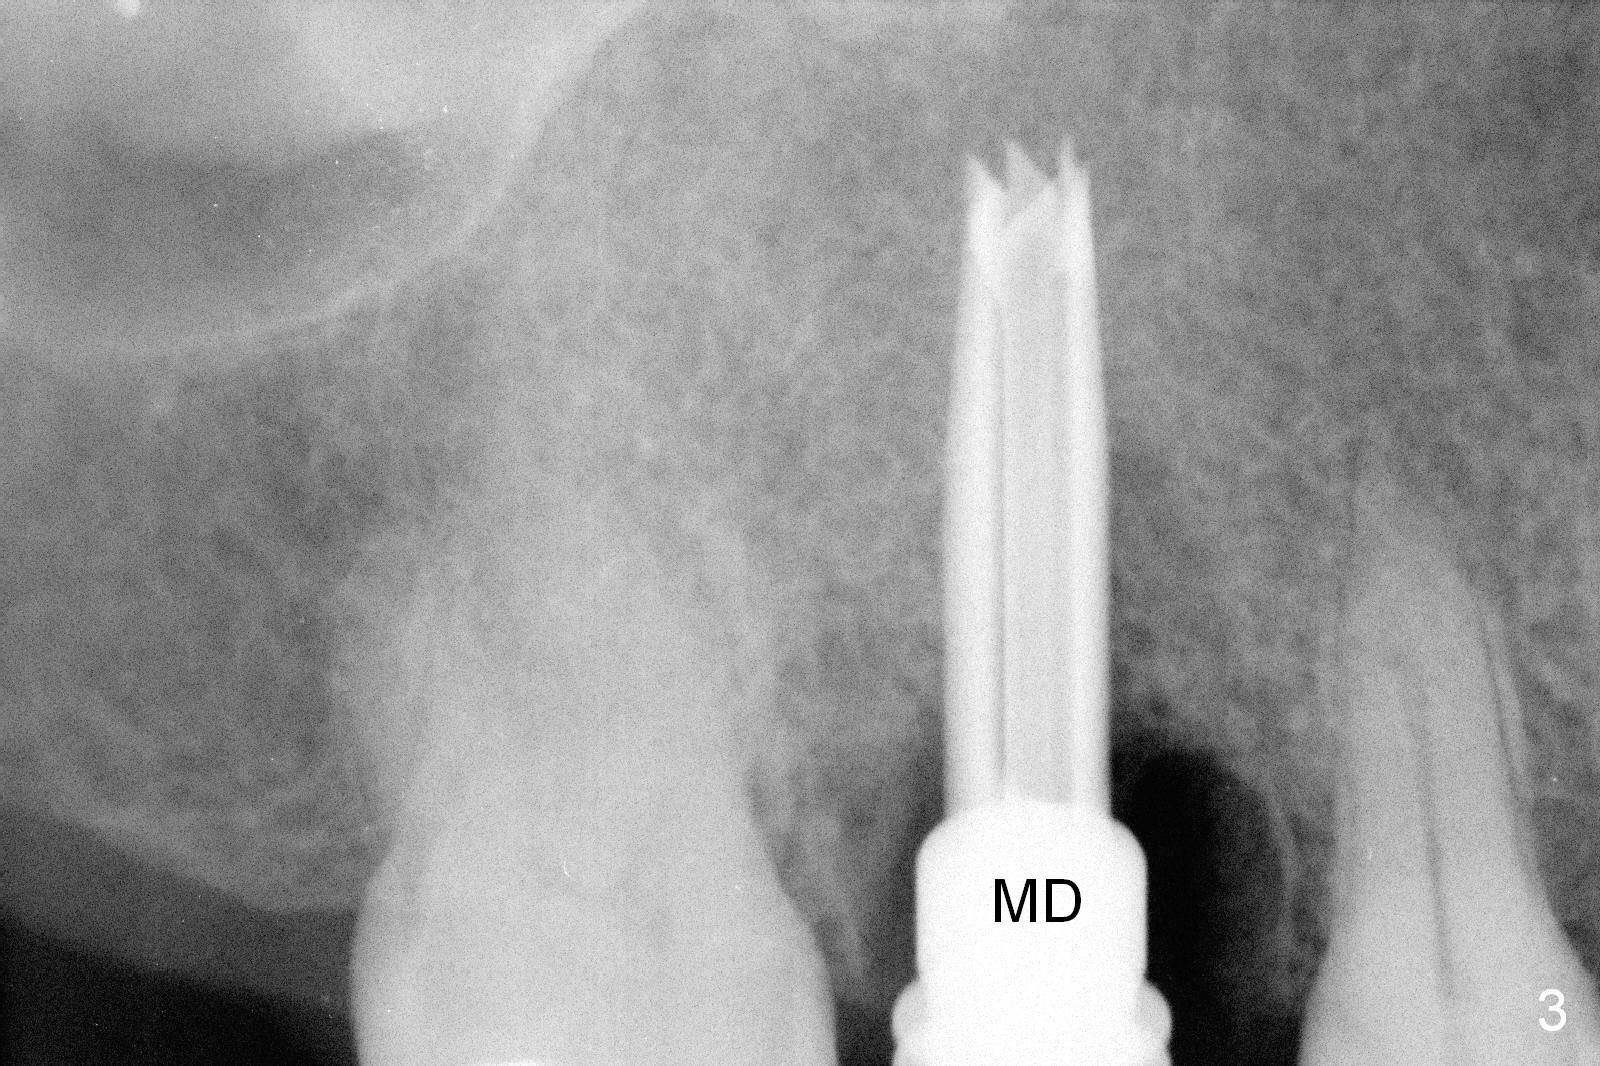

The polyp in the pulpal chamber of the tooth #3 (Fig.1) originates from the distal gingiva. After extraction, buccal plate perforation is found apical to the distobuccal socket. The septum is large (Fig.2 S). Osteotomy is initiated in the middle of the septum with 1.6 mm drill until 3.8 mm Magic Drill (MD) (Fig.3). The last drill is 4.3 mm, followed by 4.8 mm Magic Expander since the palatal wall of the osteotomy is thin after the last drill. A 5x13 mm IBS implant is placed with ~ 45 Ncm. The apical portion of the 3 sockets is filled with Osteogen plug and the coronal portion with autogenous bone (harvested from MD), mixed with allograft and Osteogen (Fig.4 * as well as collagen plug in the most superficial portion of the sockets). A 6.5x4(4) mm pair abutment (Fig.4 A) is placed to hold an immediate provisional in place.